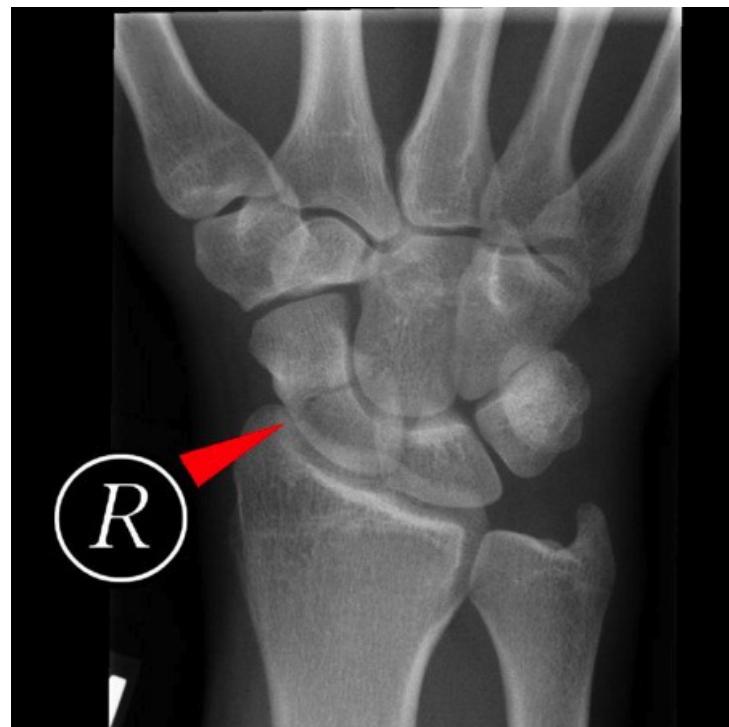

Scaphoid Fracture

- Diagnosis: Scaphoid Fracture.

- Clinical Sign: Tenderness in the anatomical snuffbox.

- Management: Thumb spica splint/cast. If X-ray is normal but tenderness is present, treat as a fracture and repeat X-ray in 10-14 days or order a CT/MRI.